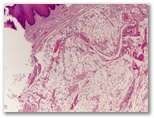

Diagnostico